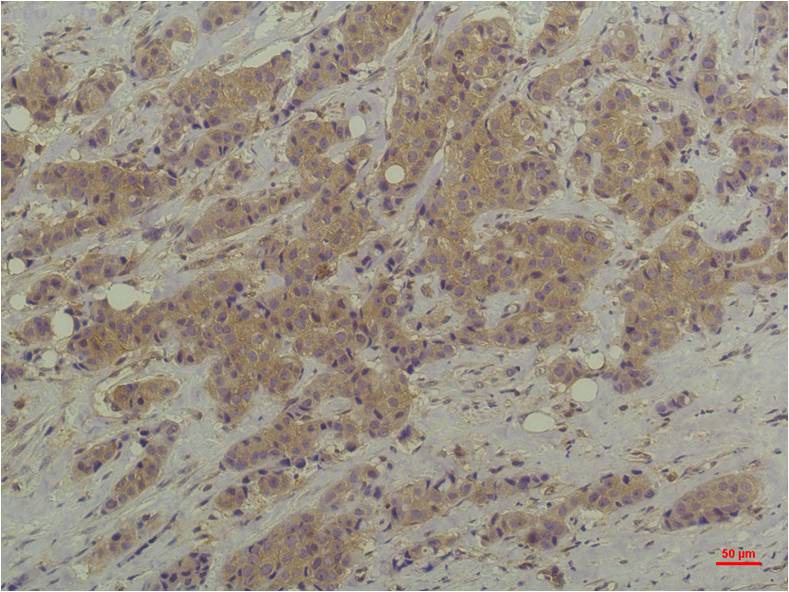

- Immunohistochemistry analysis of paraffin-embedded Human Breast Carcinoma using ERK1/2 antibody.High-pressure and temperature Sodium Citrate pH 6.0 was used for antigen retrieval.